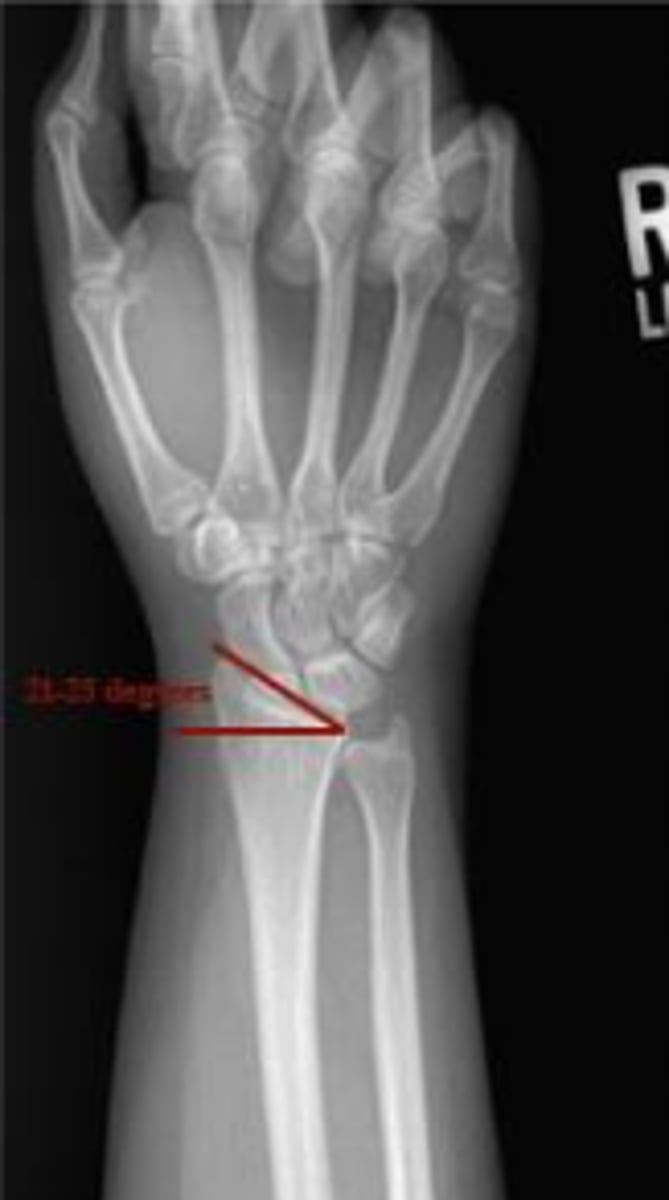

Radial inclination

What is the name of the assessments

Yes

Is the given range within normal limits?